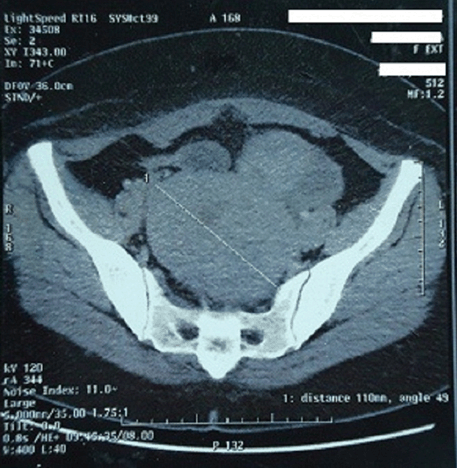

Histopathological examination revealed a tumorous proliferation with fasciculated appearance made up of smooth muscle cells with diffuse moderate to severe atypia (Figure 2). Some fields contained quite numerous mitoses, but the mitotic count did not exceed eight to nine mitoses per ten high power fields (Figure 3). Furthermore, tumor proliferation was dissociated by enlarged foci of fibrosis. There was no tumor necrosis. On the other hand, both of the cervix, the endometrium, the fallopian tubes and the left ovary were substantially normal. According to these histologic findings, our case was diagnosed as uterine smooth muscle tumor of uncertain malignant potential (STUMP).

Figure 2: Smooth muscle proliferation with moderate atypia (H&E stain, x200).